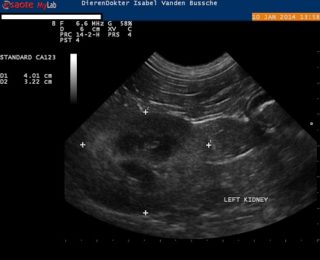

Er is ook een echografietoestel aanwezig in de praktijk, waarmee we de baarmoeder (vb. bij zwangerschap, baarmoederontsteking, …), de blaas, de darmen, de maag, de milt, de lever, … kunnen in beeld brengen en dus onderzoeken.